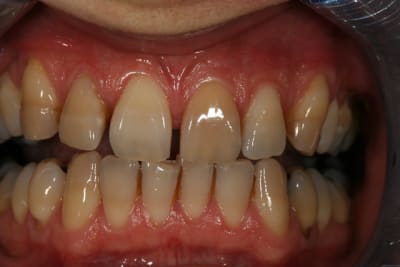

Un cas de blanchiment interne .

Cas simple et pourtant ... j'ai été obligé de prendre un risque . Lequel ?

Indice : on lui avait proposé la dévit et une céram .

Un rapport avec la fissure vestibulaire qui semble se poursuivre en sous gingival?

C'est un blanchiment interne comme si l'endo était faite (après recherche effrénée d'un hypothétique canal), et après contrôle +++ d'une isolation +++ . La patiente n'a aucun souvenir d'un traumatisme sur cette dent .